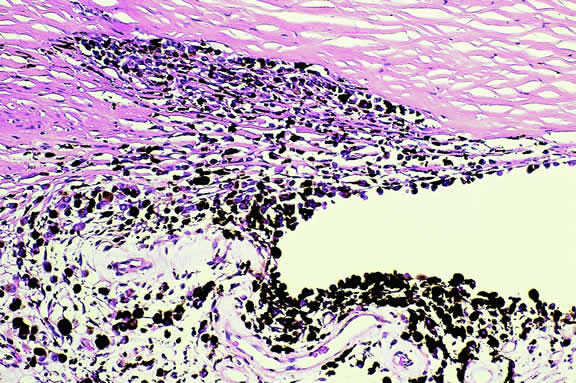

A rare type of secondary glaucoma called melanocytomalytic glaucoma may develop in patients who have partially necrotic melanocytomas of the iris and ciliary body.25, 26, 27 In such cases, the open angle is obstructed by macrophages that have ingested melanin pigment released by the necrotic tumor (Fig. 7).

Fig. 7. Melanocytomalytic glaucoma. Macrophages that have phagocytosed melanin pigment dispersed by necrotic melanocytoma fill peripheral anterior chamber and infiltrate trabecular meshwork.